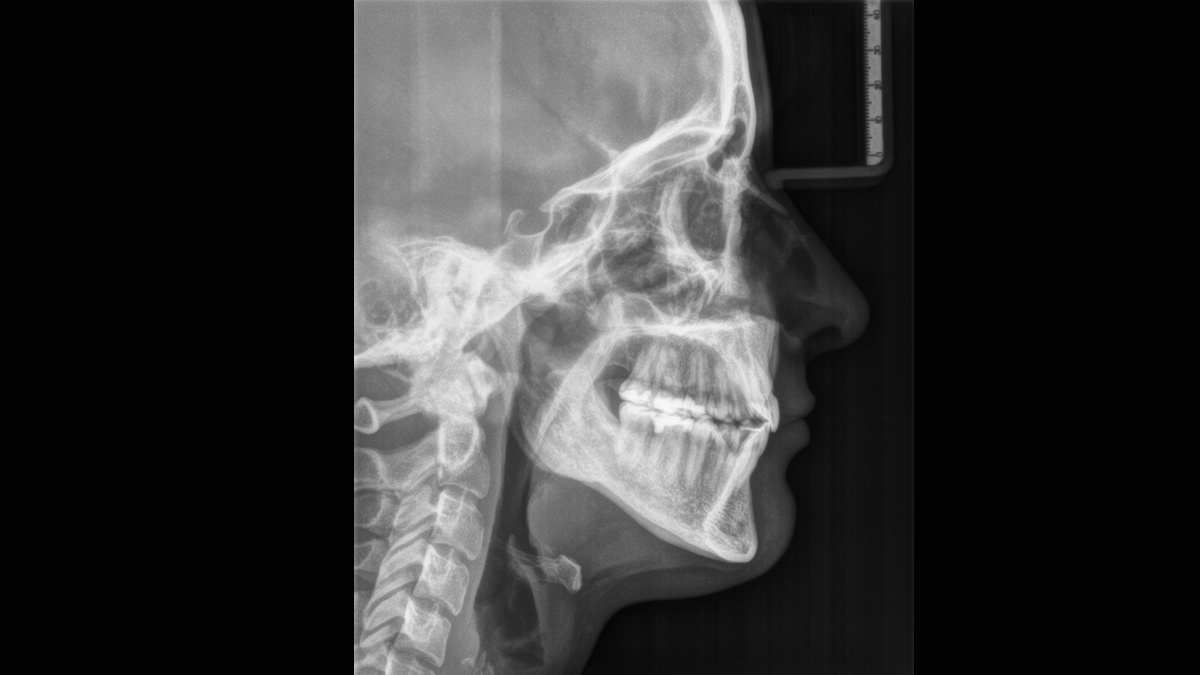

L’unité de radiographie 2D permet de s’immerger facilement dans le monde de l’imagerie numérique. Grâce à la technologie de capteur CsI et à son interface simple, vous bénéficiez de diagnostics fiables à chaque fois. L’option céphalométrique fait également de l’Orthophos E un partenaire fiable pour l’orthodontie. Dotez votre cabinet d’une large gamme de services qui ne sont possibles qu'avec l'imagerie numérique.

Pour un soutien diagnostique optimal en orthodontie, un bras céphalo à gauche peut être commandé ou installé à tout moment